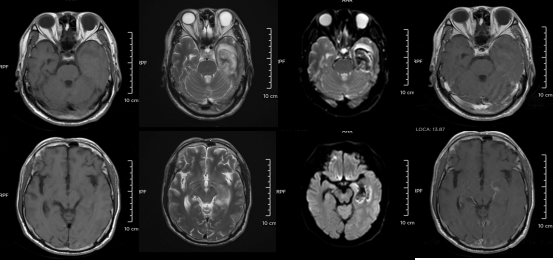

△某单纯疱疹病毒性脑炎患者的医学影像。图源:浙江大学医学院附属第二医院